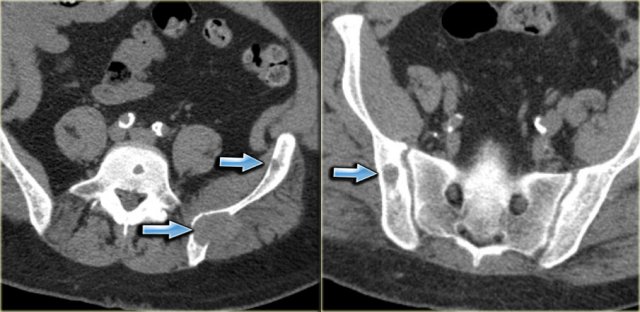

Here CT-images of a patient with renal failure and multiple well-defined osteolytic lesions.

The differential diagnosis included metastases, multiple myeloma and Brown tumors in hyperparathyroidism.

Biopsy revealed Brown tumor.